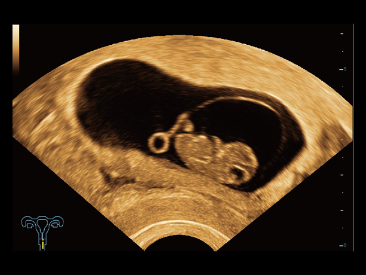

Oprócz uzyskiwania jako?ci obrazu typowego dla aparatów klasy premium, Resona 7 rozszerza mo?liwo?ci klinicznych badań USG dzi?ki rewolucyjnej funkcji V Flow, s?u??cej do oceny hemodynamiki naczyń, a tak?e najlepszej na rynku funkcji inteligentnego, automatycznego uzyskiwania p?aszczyzny na podstawie zestawów danych obj?to?ciowych 3D, umo?liwiaj?cej diagnozowanie stanu Centralnego Uk?adu Nerwowego u p?odu. Aparat Resona 7 ??czy w sobie najbardziej intuicyjn?, wielodotykow? obs?ug? za pomoc? gestów oraz wszystkie kluczowe funkcje kliniczne, co sprawia i? jest prawdziwym liderem we wprowadzaniu innowacji w ultrasonografii.